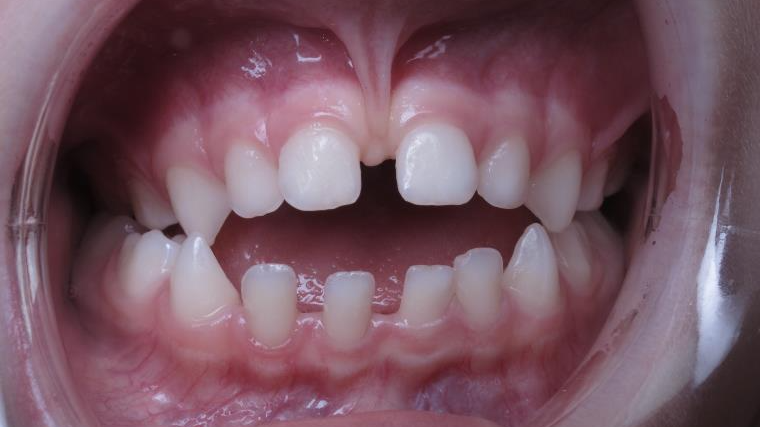

Sélectionnez les différentes étapes du traitement pour comparer et analyser la dentition du cas clinique.

surveillance évolution de la dentition

bilan de début et en cours de traitement